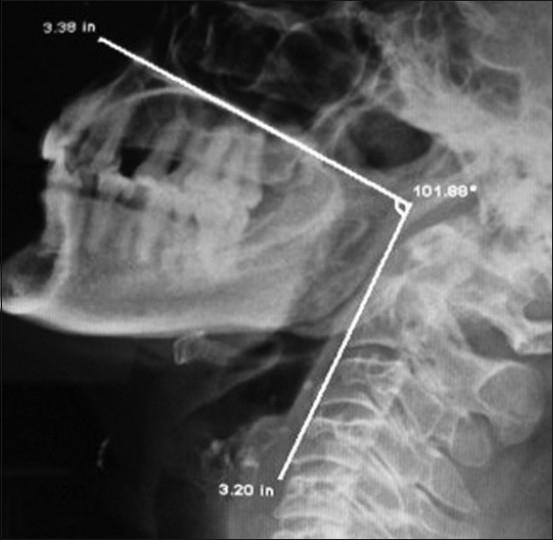

Difficult airway continued to be a major cause of anesthesia-related morbidity and mortality. Successful airway management depends on direct laryngoscopy and tracheal intubation. Difficult laryngoscopy is a resultant of incomplete structural arrangements during the process of head positioning. Through clinical history, examination of the patients along with craniofacial indices alerts the anesthetist for difficult laryngoscopy. But it does not predict all causes of difficult laryngoscopy during pre-anesthetic evaluation. The maxillo-pharyngeal angle, an upper airway anatomical balance, was proposed for better understanding the pathophysiology of difficult laryngoscopy. In our study we have assess difficult laryngoscopy by electronically measuring maxillo-pharyngeal angles on a lateral cervical radiograph. This angle is normally greater than 100°. Less than 90° angle suggests either impossible or difficult direct laryngoscopy when all known craniofacial indices were within the normal range. Cervical radiographic assessment is a simple, economical, and non-invasive predictive method for difficult laryngoscopy. It should be used routinely along with other indices as pre-anesthetic airway assessment criteria to predict the difficult laryngoscopy.

In 148 patients (94.28%), the maxillo-pharyngeal angle was more than 100°, in 7 patients (4.45%) it was less than 90°, and in 2 patients (1.27%) the M-P angle was less than 85° with normal craniofacial indices. When the MP angle was less than 90°, the direct laryngoscopy was difficult which could be compared with to Cormack and Lehane classification grade III and IV.

148例患者(94.28%)的上颌 - 咽角大于100°,7例患者(4.45%)小于90°,2例患者(1.27%)的M - P角小于85°且颅面指数正常。当MP角小于90°时,直接喉镜检查困难,可与Cormack和Lehane分级III级和IV级相比较。